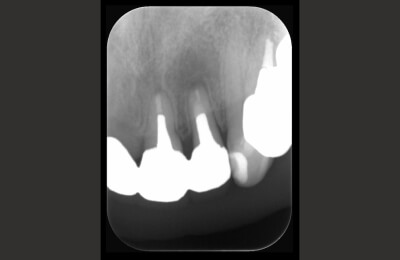

精密根管治療症例

術前

治療中

矢印部が処置されていない

術後

矢印部に大きな骨吸収像

根管を清掃した後

骨の再生が見られる

| 主訴 | 噛むと違和感がある。 レントゲンで根の先に黒い影を指摘された。 |

|---|---|

| 治療期間 | 根管治療3回 補綴治療3回 |

| 治療費 |

(ファイバーコア・ジルコニアクラウン) |

| 治療内容 |

通法の根管治療を行いました。ラバーダム防湿、 マイクロスコープ下で未処置であった根管を発見し処置。 |

| 治療のリスク |

治療直後は反応性に一時的な腫れや痛みが出る可能性があります。 根管治療で改善が見られない場合は外科的根管治療が必要になる場合があります。 |